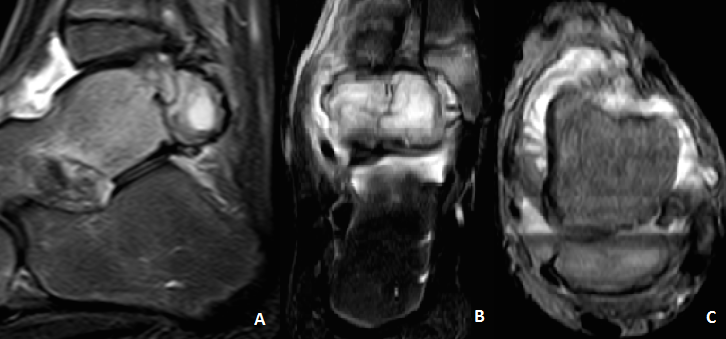

A doença de Trevor ou displasia epifisária hemimélica é uma doença esquelética rara, não-hereditária, que corresponde a uma exostose osteocartilaginosa localizada em uma ou mais epífises. Descreve-se o caso clínico de uma criança do sexo masculino, que foi admitida no serviço de urgência de ortopedia no contexto de entorse não complicada do tornozelo esquerdo. Na admissão apresentava dor e tumefação naquela articulação, associada a limitação da mobilidade e claudicação nos seis meses anteriores. Foi feita avaliação imagiológica - radiografia convencional, tomografia computorizada e ressonância magnética - que sugeriu a existência de um osteocondroma justa-articular, ao nível do tálus. Foi feita a exérese da referida exostose. A avaliação histológica concluiu tratar-se de um osteocondroma, confirmando a hipótese diagnóstica de displasia epifisária hemimélica do tálus.Downloads